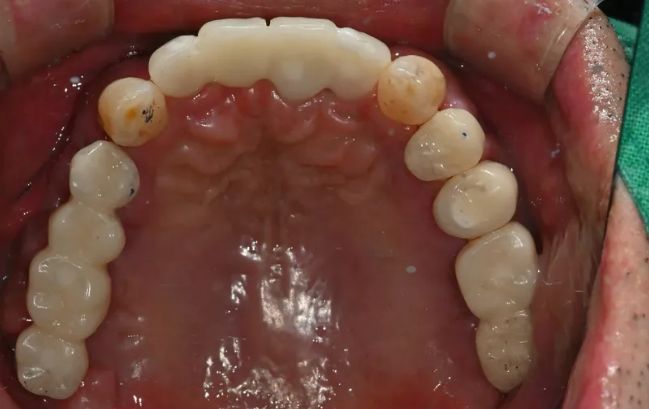

2021-09-06

2022-03-0560대 남성, 수면 전체 임플란트 13개 식립